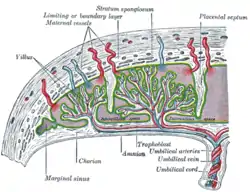

In preparation for implantation of the blastocyst, the endometrium undergoes decidualization. Spiral arteries in the decidua are remodeled so that they become less convoluted and their diameter is increased. The increased diameter and straighter flow path both act to increase maternal blood flow to the placenta. There is relatively high pressure as the maternal blood fills intervillous space through these spiral arteries which bathe the fetal villi in blood, allowing an exchange of gases to take place. In humans and other hemochorial placentals, the maternal blood comes into direct contact with the fetal chorion, though no fluid is exchanged. As the pressure decreases between pulses, the deoxygenated blood flows back through the endometrial veins.

Fetoplacental circulation

Deoxygenated fetal blood passes through umbilical arteries to the placenta. At the junction of umbilical cord and placenta, the umbilical arteries branch radially to form chorionic arteries. Chorionic arteries, in turn, branch into cotyledon arteries. In the villi, these vessels eventually branch to form an extensive arterio-capillary-venous system, bringing the fetal blood extremely close to the maternal blood; but no intermingling of fetal and maternal blood occurs ("placental barrier").[20]

Endothelin and prostanoids cause vasoconstriction in placental arteries, while nitric oxide causes vasodilation.[21] On the other hand, there is no neural vascular regulation, and catecholamines have only little effect.[21]